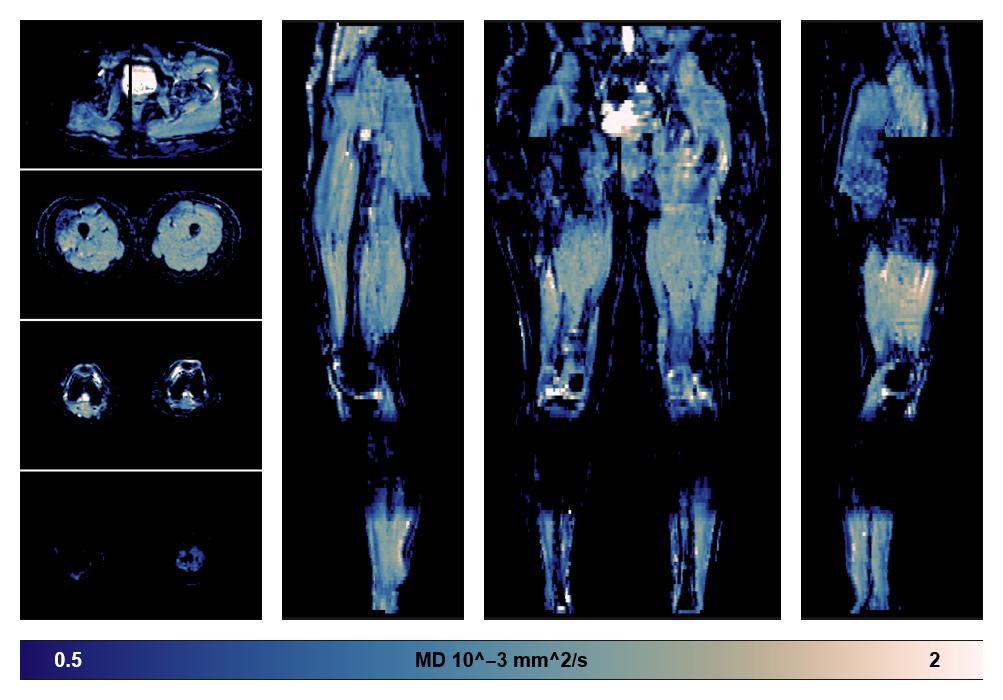

• Mean diffusivity

IVIM corrected whole leg muscle mean diffusivity obtained from diffusion tensor imaging.